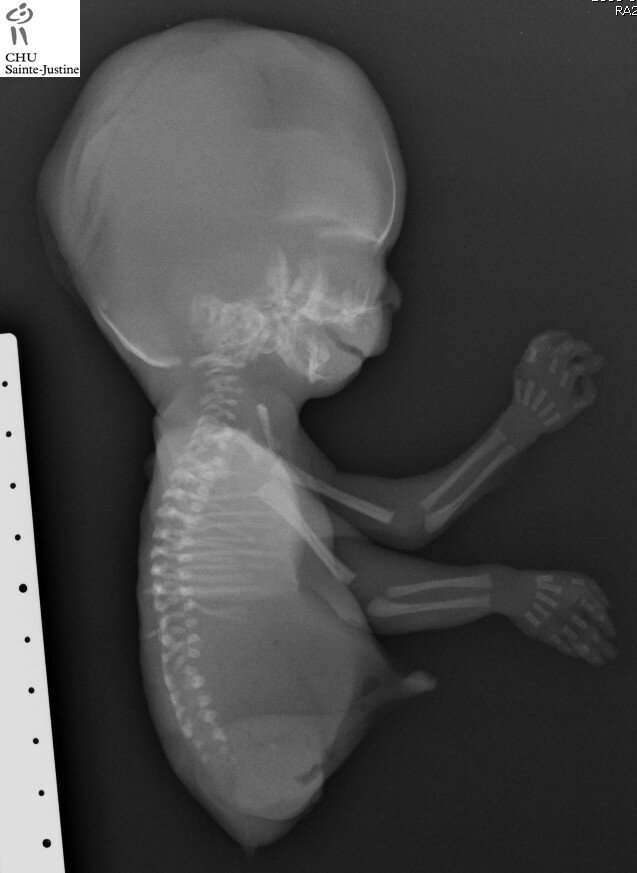

caudal dysplasia with agenesis of lower limbs

maternal diabetes

caudal dysplasia

lower limb agenesis